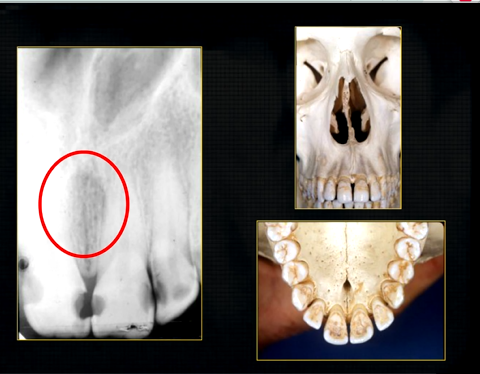

what does this anterior periapical graph show?

oval radiolucent area between the central incisors - is it Infront of the teeth (buccally?) or is it behind them? - you can’t tell radiographically

but its shape and position is compatible with the palatally positioned with the nasopalatine formaina

more posteriorly - radiopacities indicate the nasal septum and floor of the nose

dense, thin , white line in the middle of the image is the nasal septum

less dense opacity is caused by the

inferior nasal concha